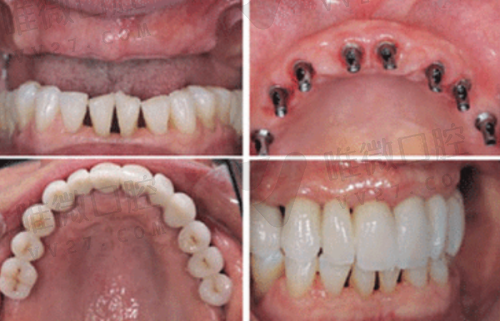

| 种植牙 | 2975元起 | 韩国仕诺康、奥齿泰、瑞士士卓曼等 | 含手术+种植体,不含牙冠 |

? “种了颗韩国奥齿泰种植牙,到现在半年用了都不影响吃排骨,值!”